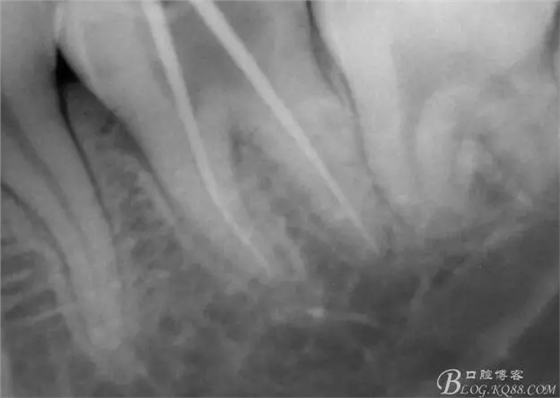

一周后復(fù)診,37叩(—)。去除暫封物,沖洗,試主尖拍片。

X線示牙膠尖到達工作長度,故行AH-PLUSH糊劑配合卡瓦熱牙膠機運用連續(xù)波充法根充,暫封拍根尖片。